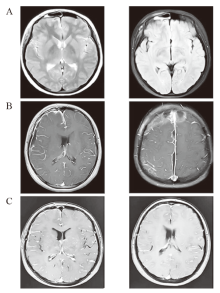

牙髓卟啉单胞菌是一种革兰阴性厌氧杆菌,常见于口腔正常菌群中。牙髓卟啉单胞菌主要引起牙源性感染,由其引发的颅内感染则极为罕见。1例10岁男性患儿因“反复高热伴面部肿胀3天,抽搐1次”收治入院。入院时患儿嗜睡,面部及颈部肿胀,布氏征阳性。实验室检查示白细胞计数26.16×109/L,C反应蛋白279.57 mg/L,降钙素原>100 ng/mL;脑脊液检查示白细胞45×109/L,蛋白945 mg/L;头颅磁共振成像示双侧额叶脓肿形成。宏基因组二代测序检测血液、脑脊液及脓液均提示牙髓卟啉单胞菌及多种厌氧菌序列。基于上述检验和检查结果,患儿明确诊断为牙髓卟啉单胞菌脑脓肿,并采用万古霉素、美罗培南、利奈唑胺及甲硝唑等抗感染治疗。使用抗生素后,患儿的临床症状一度好转,但热度反复,影像学提示脓肿扩大伴中线移位。于入院第14天为患儿行颅骨硬膜下及硬膜外脓肿清创术。术后继续抗感染治疗6周,患儿体温恢复正常,脓肿吸收,痊愈出院。

Porphyromonas endodontalis is a Gram-negative anaerobic bacterium commonly found in the normal oral flora and is primarily associated with odontogenic infections. Intracranial infections caused by this bacterium are extremely rare. In January 2023, a 10-year-old male was admitted to hospital due to recurrent high fever accompanied by facial swelling for 3 days and one episode of convulsion. Physical examination revealed drowsiness, swelling of the face and neck, and a positive Brudzinski's sign. Laboratory tests showed a white blood cell count of 26.16×109/L, C-reactive protein of 279.57 mg/L, and procalcitonin >100 ng/mL. Cerebrospinal fluid analysis indicated a white blood cell count of 45×109/L and a protein level of 945 mg/L. Head magnetic resonance imaging revealed the formation of bilateral frontal lobe abscesses. Metagenomic next-generation sequencing of blood, cerebrospinal fluid, and pus detected sequences of Porphyromonas endodontalis and various other anaerobic bacteria. A definitive diagnosis of a brain abscess caused by Porphyromonas endodontalis was established. Although initial antimicrobial therapy with vancomycin, meropenem, linezolid, and metronidazole led to transient clinical improvement, the patient experienced recurrent fever, and follow-up imaging showed abscess enlargement with a midline shift. Subsequently, surgical debridement of the subdural and epidural abscesses was performed on the 14th hospital day. Postoperative anti-infective therapy was continued for 6 weeks, resulting in the resolution of fever, absorption of the abscess, and eventual recovery upon discharge.